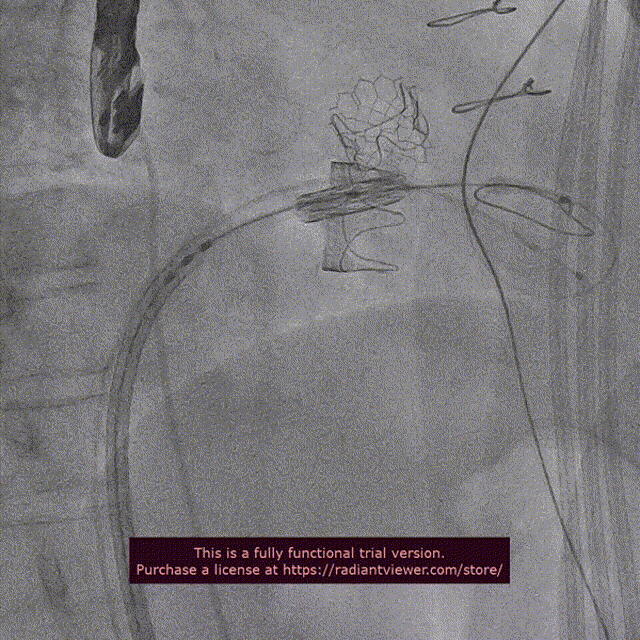

近日,中国医学科学院阜外医院潘湘斌教授团队,在多科室的通力配合下,凭借扎实的手术功底顺利完成一例经导管主动脉瓣和二尖瓣瓣中瓣置换术。

手术过程